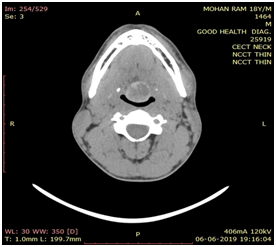

We present a case of a 18 years old male who presented to our outpatient clinic with chief complaints of persistent cough and foreign body sensation since one month. He was completely asymptomatic before that. There was no history of weight loss, prolonged fever, sputum production and sore throat. There was no history suggestive of hypothyroidism. On examination, there was a small soft cystic midline swelling of size 4x3 cm at the base of tongue extending to left lateral side (Figure 1). It was not bleeding on touch. Neck examination revealed absence of thyroid gland on palpation. There were no palpable neck nodes. Indirect laryngoscopy showed bilateral vocal cord mobility with normal endolarynx. Ultrasound neck showed absence of thyroid gland in normal anatomical location. Thyroid function test revealed T3- 1.31 ng/ml, T4-8.7ug/dl, TSH-24.18uiu/ml. After getting endocrinology opinion, patient was started on 50 microgram of L-thyroxine. Further evaluation in the form of contrast enhanced computed tomography scan neck revealed cystic swelling of 3x2 cm size with peripheral rim of enhancement suggestive of thyroid tissue at the base of tongue and absence of thyroid gland in normal anatomical location (Figure 2). Technetium 99m scan suggested increased isotope uptake at base of tongue and no uptake at the normal thyroid location.

Figure 2 CECT scan showing a well-defined cystic swelling (indicated by arrow) of 3x2cm size with peripheral rim of enhancement at base of tongue. (Axial and Sagittal view).